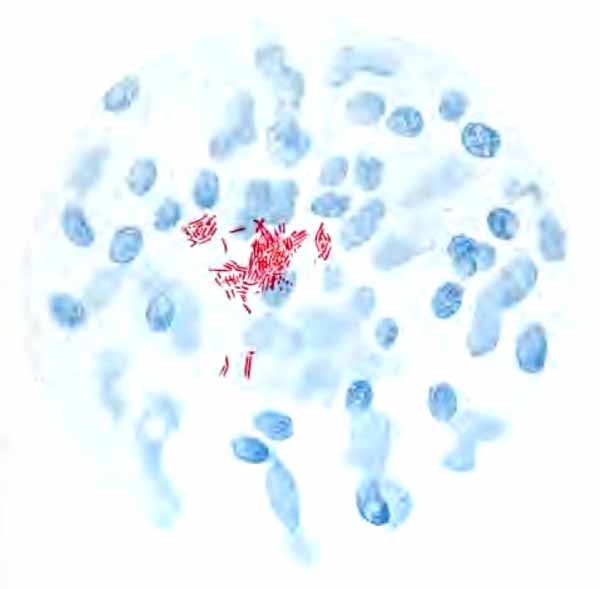

In films stained by Gabbet's method tubercle bacilli, if present, will be seen as slender red rods upon a blue background of mucus and cells (Plate II, Fig. 2). They average 3 to 4 µ in length—about one-half the diameter of a red blood-corpuscle. Beginners must be warned against mistaking the edges of cells, or particles which have retained the red stain, for bacilli. The appearance of the bacilli is almost always typical, and if there seems room for doubt, the structure in question is probably not a tubercle bacillus. They may lie singly or in groups. They are very frequently bent and often have a beaded appearance. It is possible that the larger, beaded bacilli indicate a less active tuberculous process than do the smaller, uniformly stained ones. Sometimes they are present in great numbers—thousands in a field of the one-twelfth objective. Sometimes several cover-glasses must be examined to find a single bacillus. At times they are so few that none are found in stained smears, and special methods are required to detect them. The number may bear some relation to the severity of the disease, but this relation is by no means constant. The mucoid sputum from an incipient case sometimes contains great numbers, while sputum from large tuberculous cavities at times contains very few. Failure to find them is not conclusive, though their absence is much more significant when the sputum is purulent than when it is mucoid.

| PLATE II |

| FIG. 1.—Heart-failure cells in sputum, containing blood-pigment, from a case of cardiac congestion of the lungs (Jakob). |

|   |

| FIG. 2.—A, Sputum showing tubercle bacilli stained with carbol-fuchsin and Gabbet's methylene-blue solution (obj. one-twelfth oil-immersion); B, sputum of anthracosis, showing particles of coal-dust stained with methylene-blue (obj. one-twelfth oil-immersion) (Boston). |

(1) Pus-corpuscles are present in every sputum, and at times the sputum may consist of little else. They are the polymorphonuclear leukocytes of the blood, and appear as rounded cells with several nuclei or one very irregular nucleus (Fig. 8 and Plate II, Fig. 2). They are frequently filled with granules of coal-dust and are often much degenerated. Such coal-dust-laden leukocytes are especially abundant in anthracosis, where angular black particles, both intra- and extra-cellular, are often so numerous as to color the sputum (Plate II, Fig. 2, B). Occasionally mononuclear leukocytes are present.